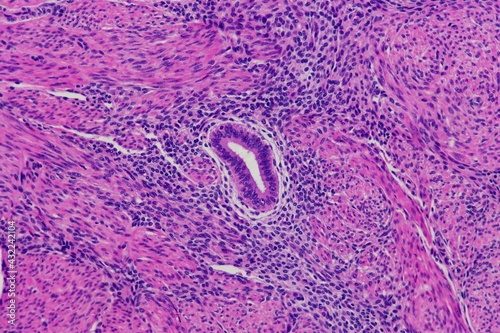

Mikrofotografi - Plakater, Poster, Billeder på lærred